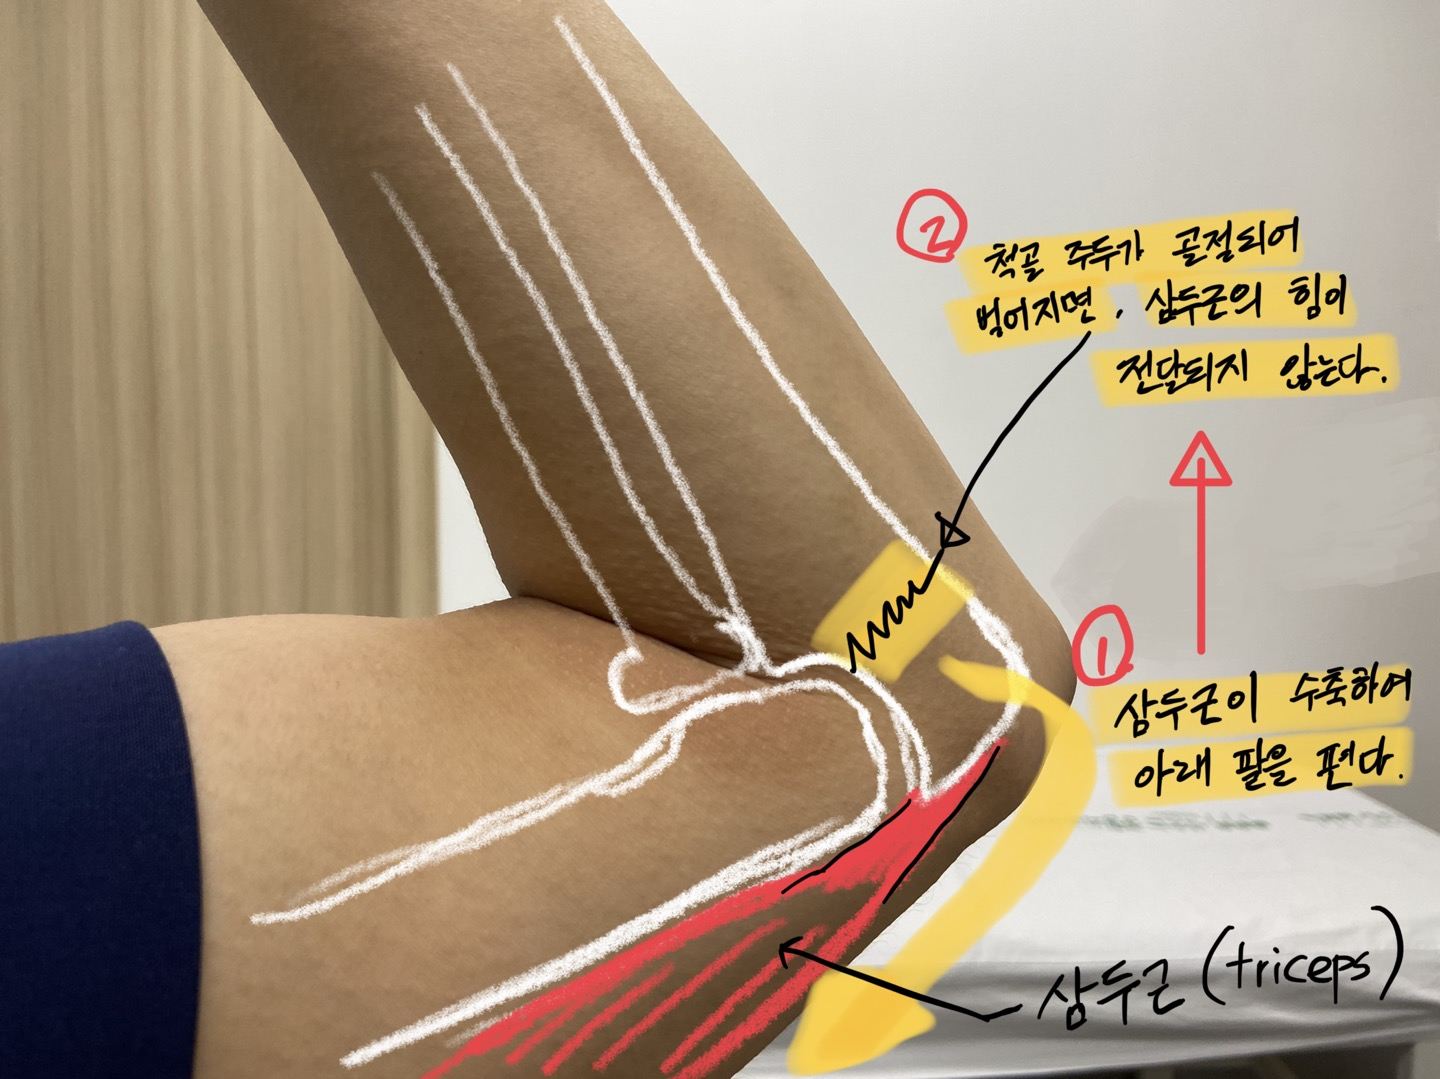

중요한 것은 저 부위가 위팔에서 내려오는 삼두근이 붙어있는 부위라는 점인데,

삼두근의 역할은 팔을 펴는 것입니다. 따라서 삼두근이 붙어있는 척골 주두가

골절이 되면, 팔을 펴는 동작이 불가능해집니다.

이러한 이유로, 척골 주두의 골절은 반드시 수술을 해야하는 케이스입니다.